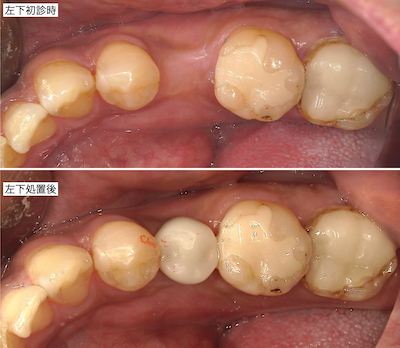

左上です。

左下です。